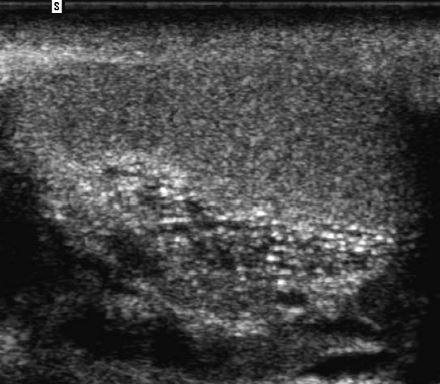

The gray-scale view shows a complex fluid

collection arising from the right kidney. In addition,

there is a simple-appearing, round, cystic structure

within the otherwise complex collection. The

power Doppler view shows flow in the apparent

cyst. All of these findings are consistent with a

pseudoaneurysm and adjacent hematoma.